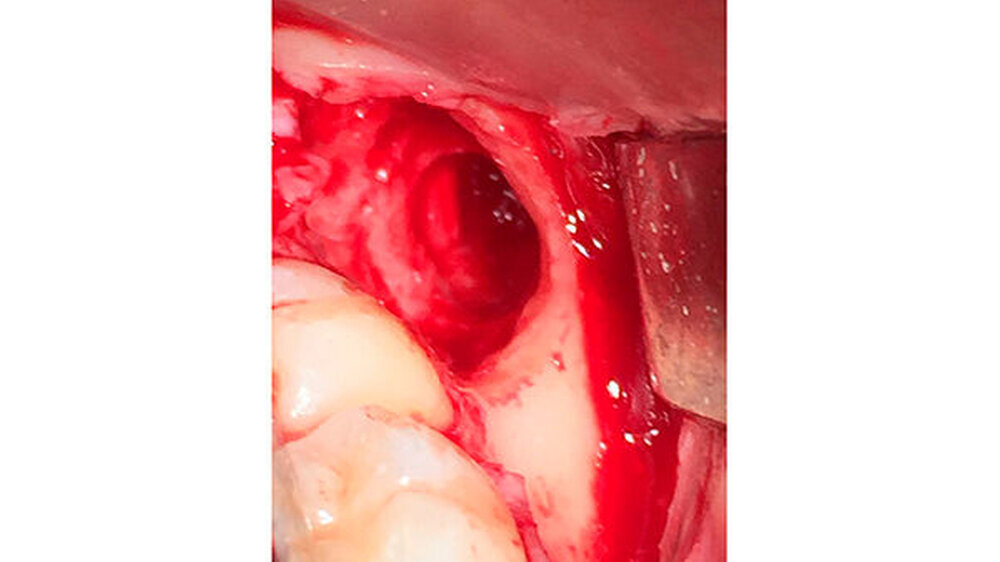

Die Zähne 28 und 18 wurden nach Aufklappung und Osteotomie schonend entfernt. Eine Mund-Antrum-Verbindung konnte intraoperativ ausgeschlossen werden. Für regio 48 wurde eine sulkuläre Schnittführung ab regio 43 gewählt, da eine eventuelle Verplattung vorgesehen war. Intraoperativ ließ sich der Zahn 48 komplikationslos in toto entfernen und die Alveole war klinisch knöchern intakt, der Nerv nicht verletzt (Abbildung 4).

Somit konnte auf eine Verplattung mittels Osteosynthese-Material verzichtet werden. In alle Extraktions-Alveolen wurde Gelatamp, Firma Roeko, eingebracht. Der Nahtverschluss erfolgte atraumatisch mit Vicryl 3/0, Firma Ethicon. Zur Dokumentation wurde postoperativ ein digitales OPG angefertigt.